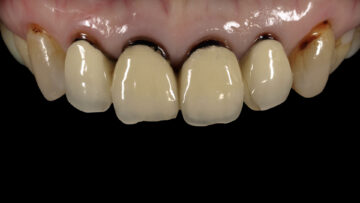

術前

術後

[治療内容] 右下6:インプラント治療 [主訴] 歯ぐきから根っこがみえているのを治したい [目的] 失った歯・歯肉の機能回復 [副作用・リスク] 術後疼痛、腫脹

インプラント周囲炎を予防するためにメインテナンスが必要[治療期間(回数)] 約12ヶ月 [費用(税抜)] ¥520,000(CT診断料、手術、被せ物)